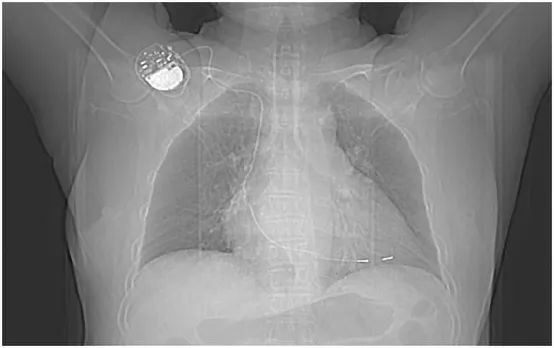

图2. 患者的胸部正位片。

图3. 患者的胸部CT检查证实起搏电极位于右室心尖。